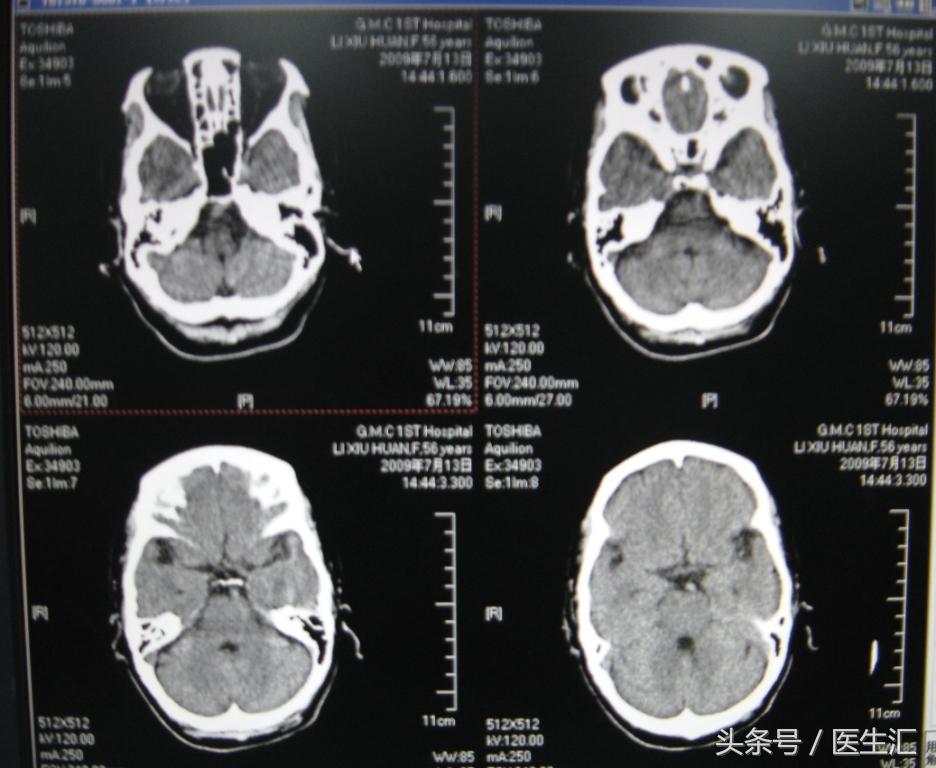

辅助检查:1、16:26CT检查平扫和灌注成像均未见明显异常(见图10、11)

2、头颅MRI、MRA及脑血管三维重建(图12、13、14)